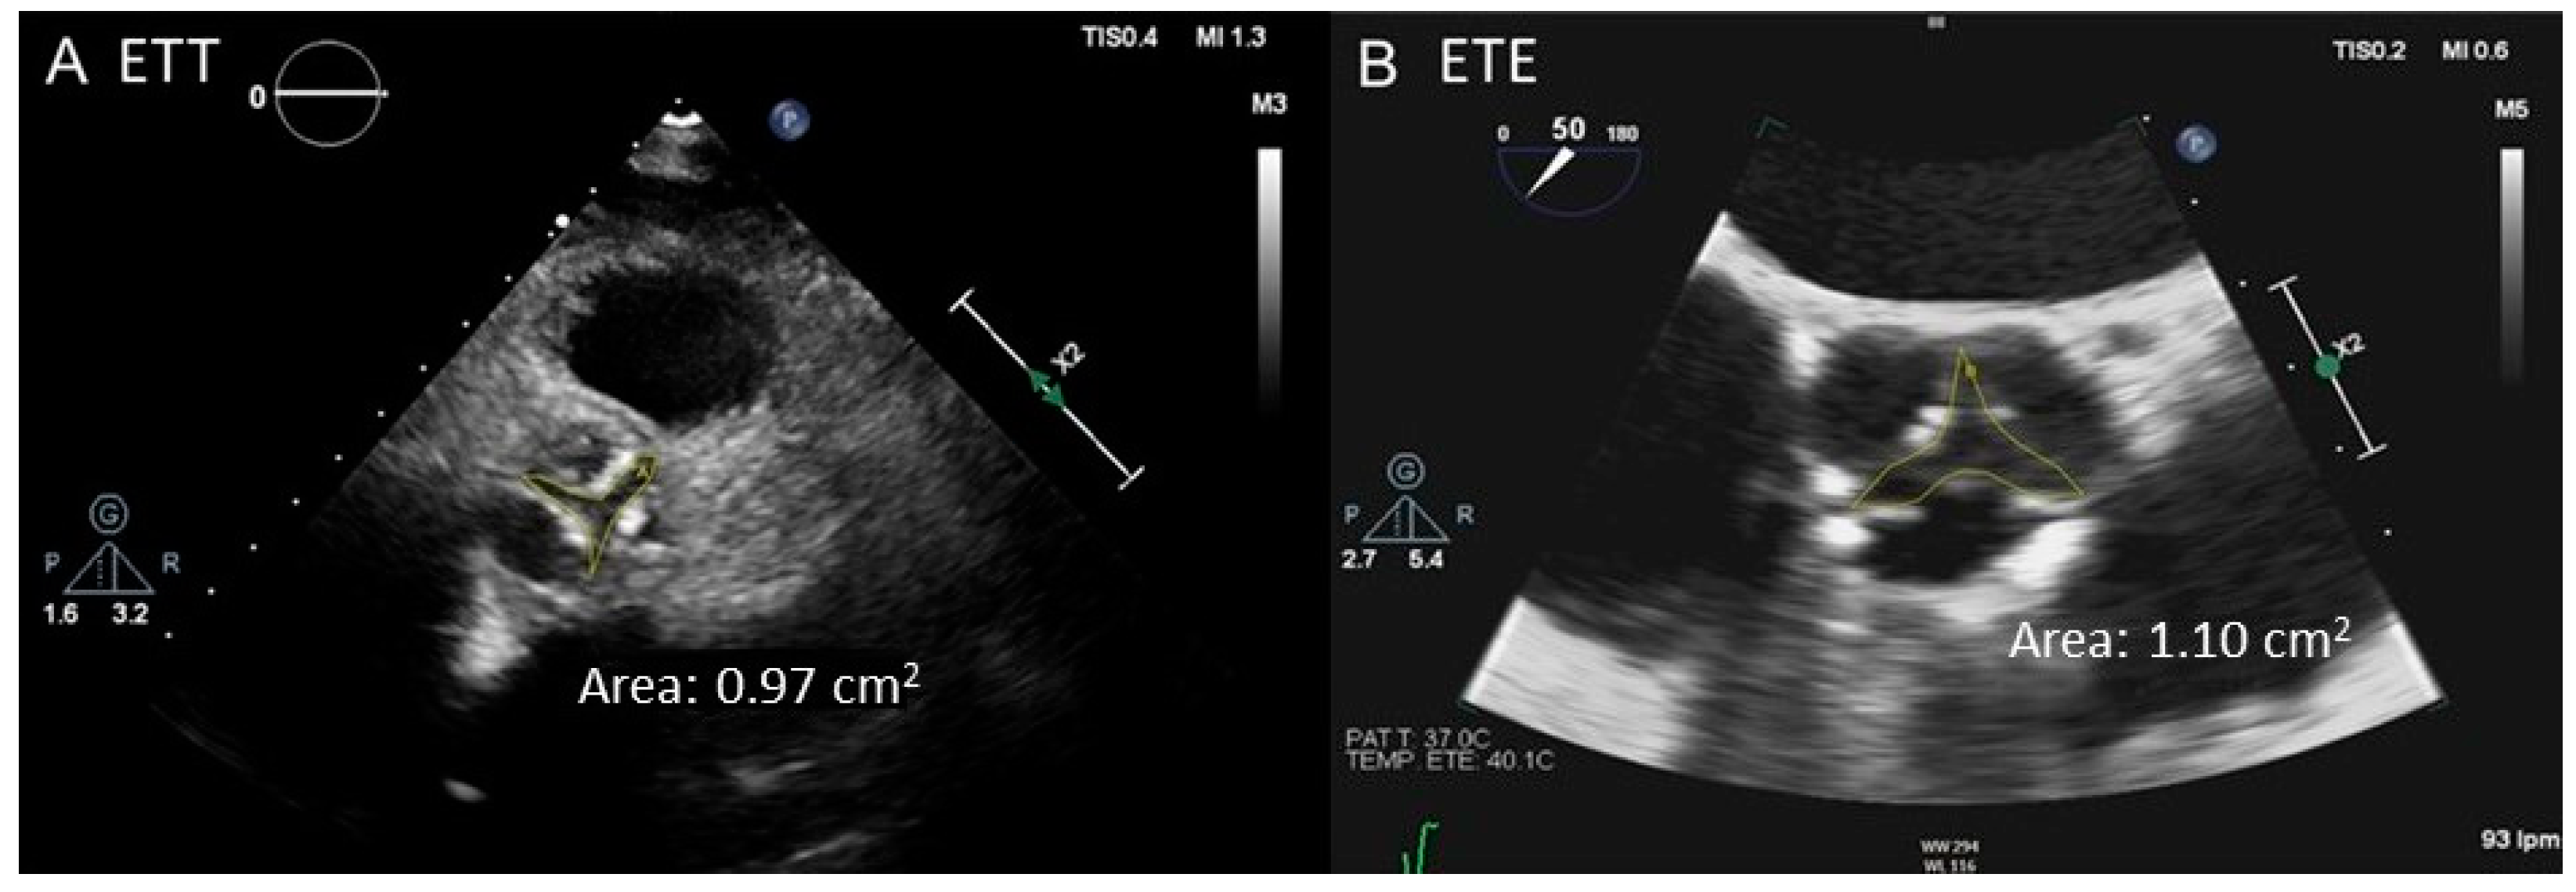

2.2. Transesophageal Echocardiography

- Planimetry. MDCT allows 3D acquisition throughout the entire cardiac cycle using retrospective protocols. Through multislice reconstructions, planimetry of the AV orifice is feasible. Such a measure has shown good agreement with AVA estimated through the CEq [40]. Concerning LVOT size, MDCT assessment is considered to be the gold standard test [23]. Clavel et al. [41] observed that AVA calculated with a hybrid TTE–MDCT method in which the LVOT area used in the Ceq was obtained with MDCT predicted long-term survival with an optimal cut-off value of 1.2 cm2 instead of 1 cm2 [41].

2.4. Cardiac Magnetic Resonance

- Planimetry. Cine sequences, selecting a perpendicular plane to the AV orifice, can be used to obtain a direct planimetry of the AVA. Such a measurement has been shown to be reproducible and correlates well with the AVA obtained by planimetry with 2D TEE [46] and with AVA estimated by catheterization [47]. Like MDCT, CMR planimetry slightly overestimates AVA compared to TTE [48]. Using Hakki’s formula, which is a simplification of Gorlin formula [49], AVA is mildly underestimated [48,50] compared to catheterization. Despite intra- and interobserver reproducibility of AV planimetry by CMR is excellent [48,50], its application is limited in certain scenarios such as the presence of a non-planar orifice, a highly calcified AV or arrhythmias (i.e., AF) [45].